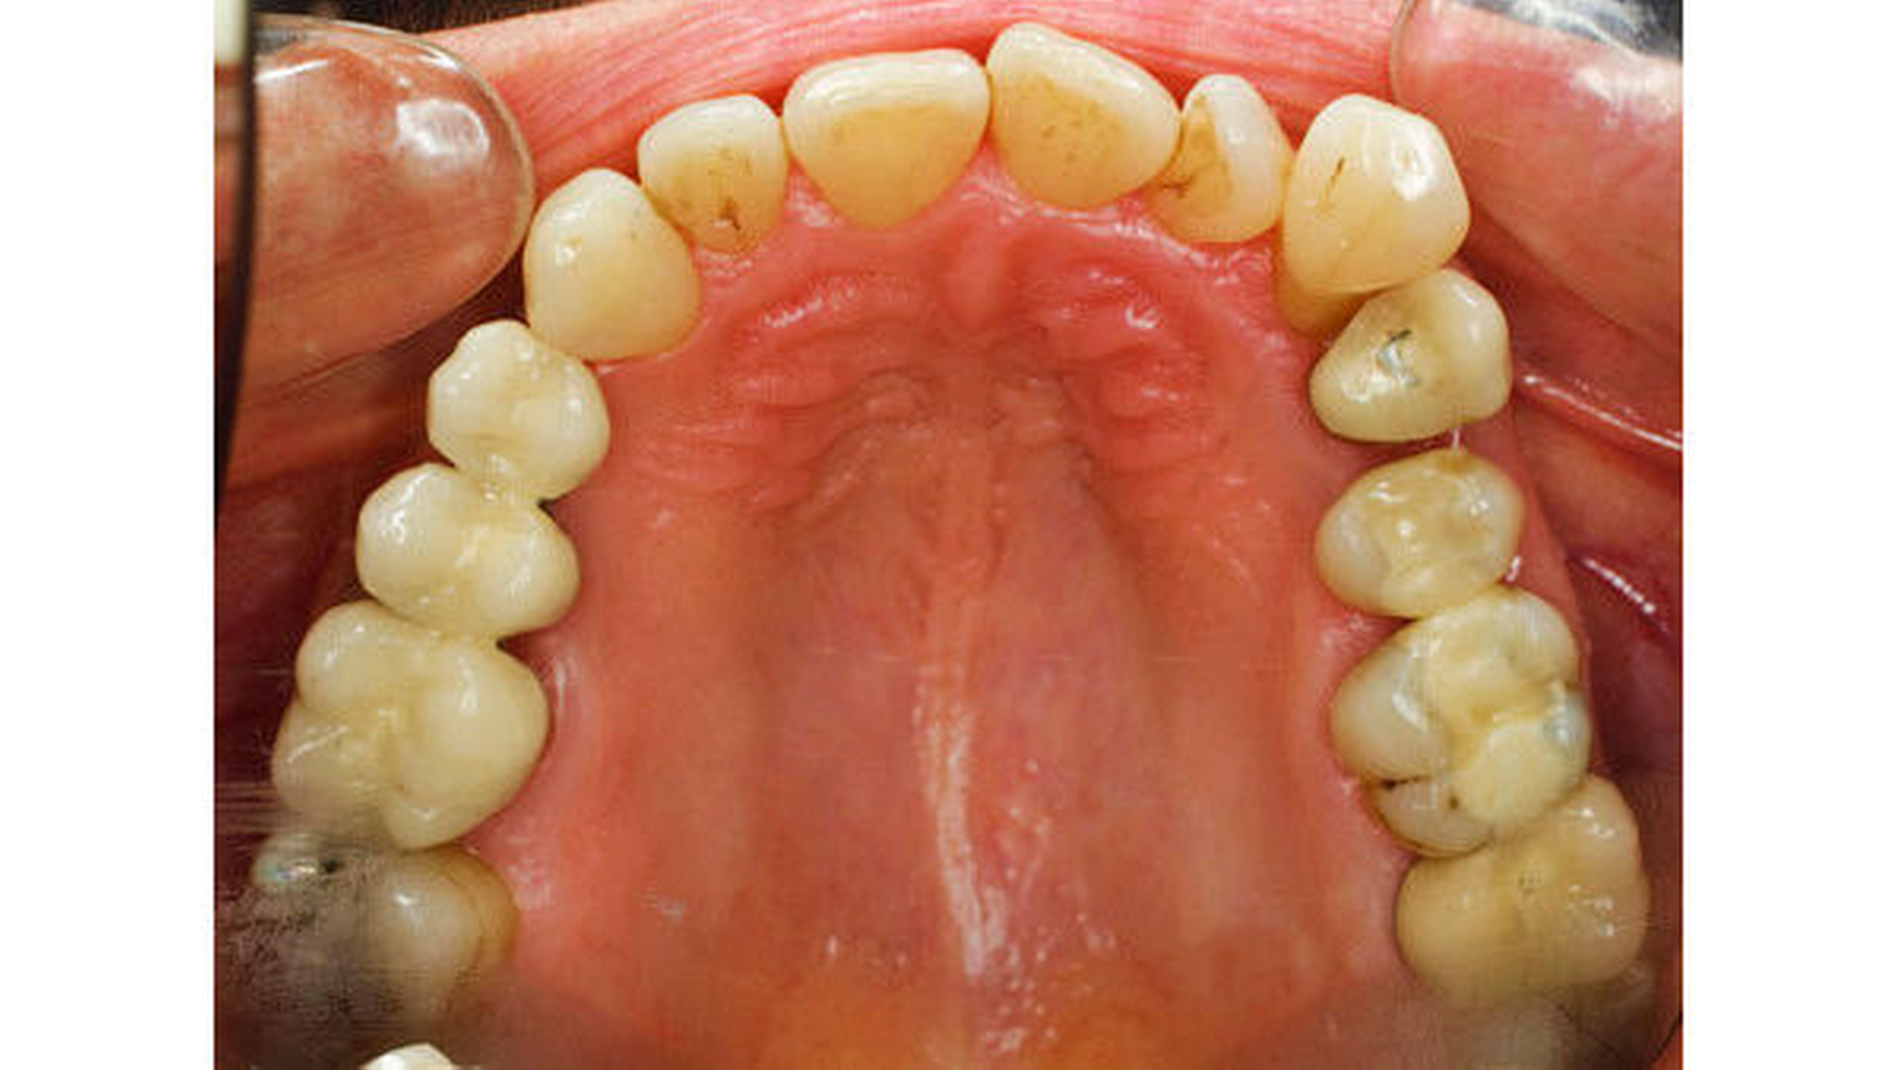

Auch wenn manche Patienten und auch einige Kollegen die Stellung der Zähne im Zahnbogen als „stabil“ bezeichnen oder wahrnehmen, zeigen Langzeitbeobachtungen in der Kieferorthopädie, dass Zähne langfristig wandern. Es müssen nicht immer Rezidive nach einer kieferorthopädischen Behandlung sein [Rudzki und Kirschneck, 2017], die die Patienten beunruhigen, es können auch ganz andere, neue Zahnwanderungen stattfinden (Abbildungen 3a bis 3c)

Heute sehen wir in den kieferorthopädischen Praxen immer mehr Patienten, die deutlich älter als 50, 60 oder gar 70 Jahre alt sind, deren Zähne so weit aus dem Zahnbogen herausgewandert sind, dass wir sie wieder „einfangen“ müssen (Abbildung 3a, Abbildungen 6a bis 6d).

Mit der Mesialdrift wird immer wieder auch die interdentale Abrasion genannt. Dies ist von prähistorischen Gebissen oder von den Zähnen bestimmter Naturvölker bekannt [Alt and Türp, 1996; Alt et al., 1998]. In ihrem Ausmaß entspricht die interdentale Abrasion aber heute oft nicht der Zahnwanderung nach mesial. Möglicherweise wären die Engstände noch deutlicher sichtbar, wenn sie gar nicht stattfinden würde. Jedenfalls wird beobachtet, dass bei einer stark eng stehenden Unterkieferfrontzahngruppe durchaus eine Mesialbewegung der Seitenbezahnung stattgefunden haben kann. Wenn die Okklusionsbeziehungen im Seitenzahnbereich gut sind, kann daraus gefolgert werden, dass auch die Seitenzähne im Oberkiefer im gleichen Takt nach mesial gewandert sind (Abbildungen 6c und 6d). Ein entsprechender Engstand in der Frontzahngruppe im Oberkiefer wird aber nicht in jedem Fall vorgefunden. In solchen Fällen ist davon auszugehen, dass im Bereich der Frontzähne des Oberkiefers in verschiedener Ausprägung ebenfalls eine gewisse interdentale Abrasion stattfindet, aber nicht im Unterkiefer: Dort haben sich die schmalen Zahnkronen durch Rotation einer interdentalen Abrasion entzogen (Abbildung 6b). Dieses Szenario wird oft beobachtet, aber es besteht durchaus noch Forschungsbedarf, um die Zusammenhänge zu verstehen.